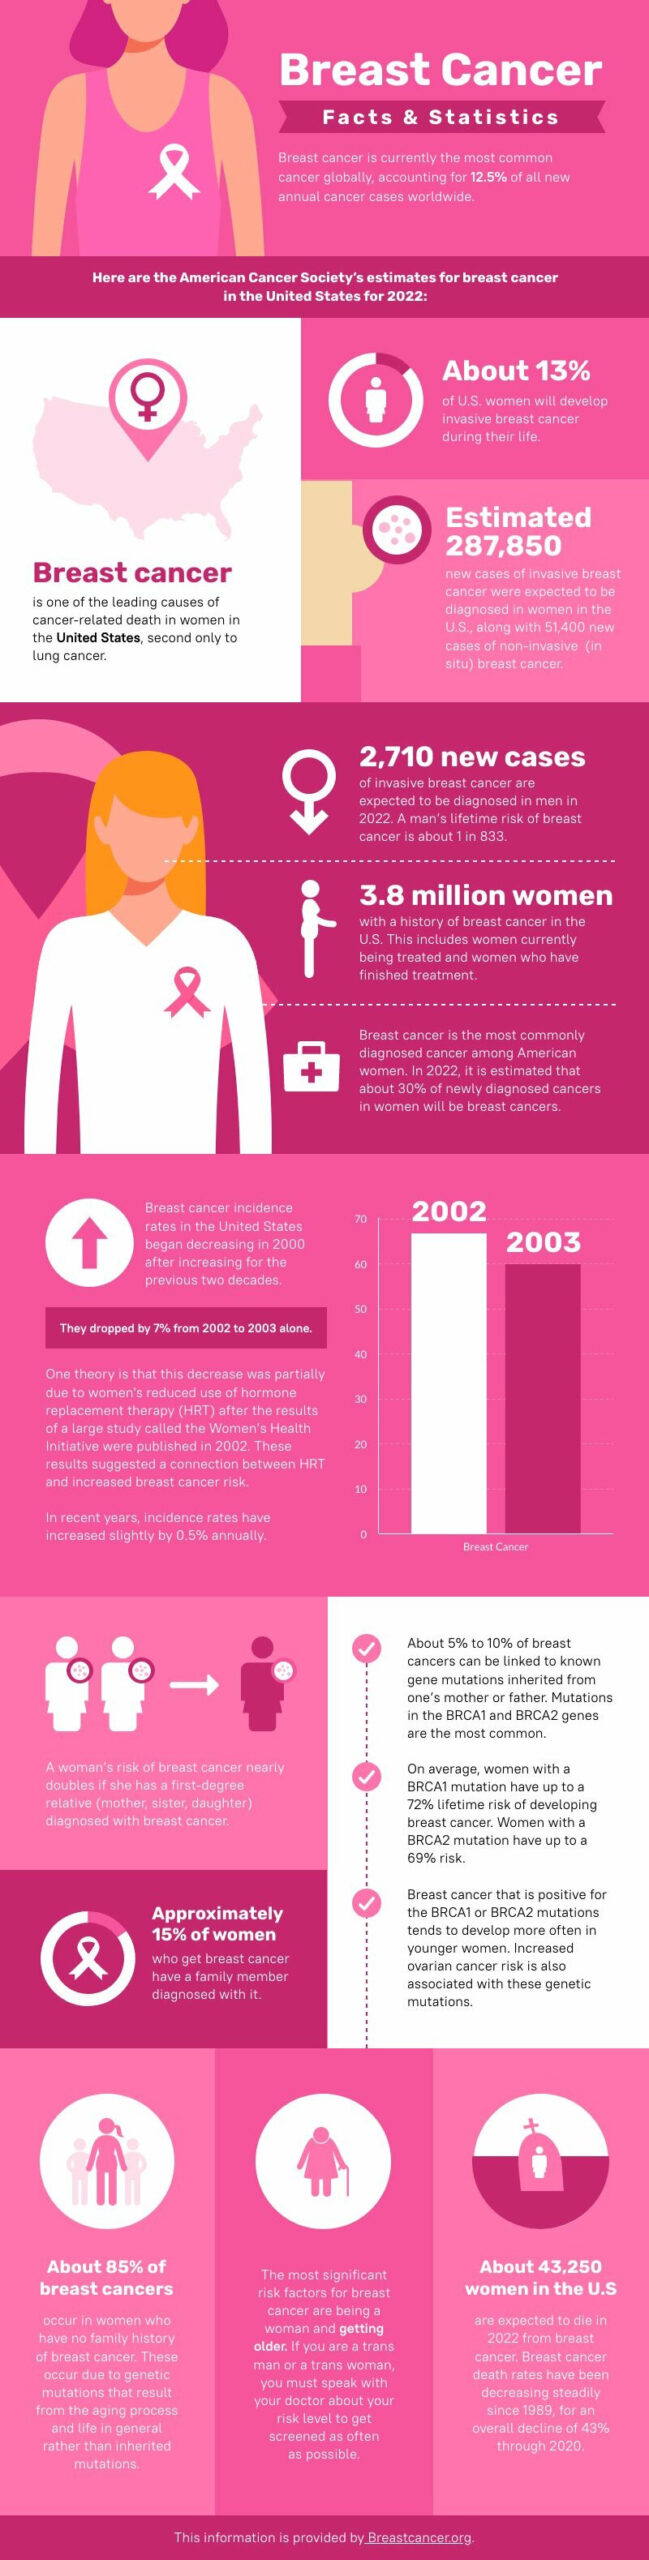

![U.S. Breast Cancer Statistics [2022]](https://www.paulsoncoletti.com/wp-content/uploads/2023/04/paulson-coletti-breast-cancer-statistics-010.png)